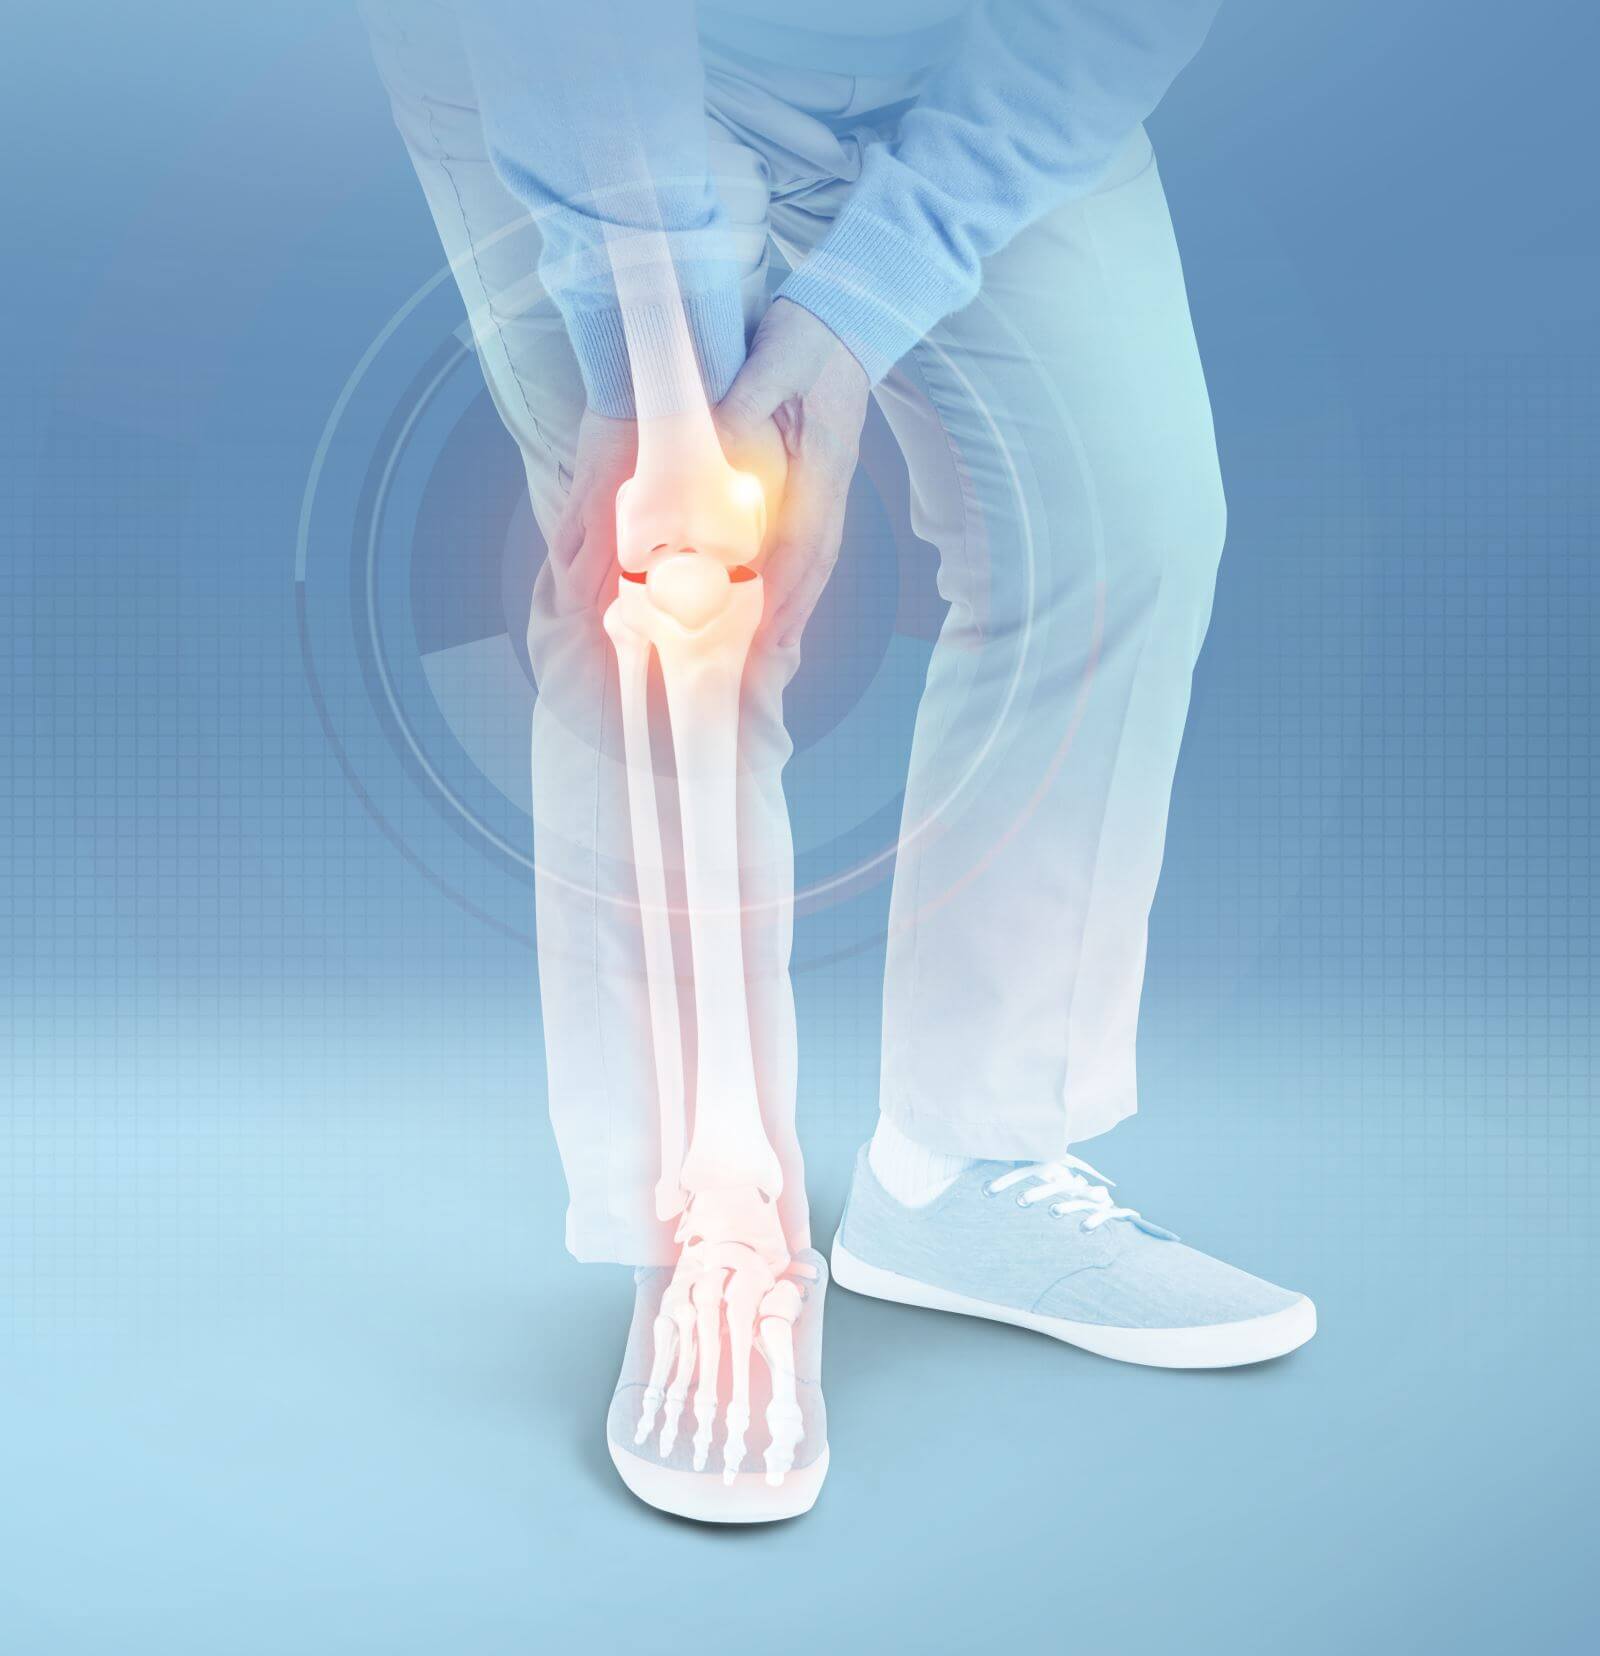

무릎 관절염 증상과 원인을 파악하고 예방방법을 알아보려고 합니다. 무릎 관절염은 관절의 연골이 손상되어 발생하는 질환으로 무릎 통증, 불편감 및 기능적 장애를 유발합니다. 이에 관련해서 자세하게 설명해 드리겠습니다.

무릎 관절염 증상

무릎 관절염 증상은 여러 가지가 있는데 그중에서 주요 증상은 무릎 통증, 강직성, 연하곤란, 관절부종, 열감 등입니다. 이러한 증상들은 점진적으로 악화될 수 있으며, 일상생활에서의 활동에 지장을 줄 수 있습니다.

1. 무릎 통증: 일반적으로 무릎 통증을 유발합니다. 이 통증은 수도 있는 느낌, 화끈거림, 당기는 느낌, 또는 뻐근한 느낌 등으로 나타날 수 있습니다.

2. 강직성: 관절 뼈 사이의 연골이 손상되면서 관절 운동 범위가 제한될 수 있습니다. 이는 강직성으로 나타날 수 있으며, 일어나거나 앉기가 어려울 수 있습니다.

3. 연하곤란: 무릎 관절염 환자는 무릎을 굽히거나 펴는 것이 어려울 수 있습니다. 이러한 연하곤란은 일상적인 활동에서 불편감을 유발할 수 있습니다.

4. 관절부종: 관절주위의 조직이 염증을 일으키며 관절부종을 유발할 수 있습니다.

5. 열감: 관절부위가 염증으로 인해 뜨거워져 더운 느낌을 유발할 수 있습니다.

이러한 무릎 관절염 증상들은 무릎 관절염의 정도와 환자의 개인적인 상황에 따라서도 다양하게 나타날 수 있습니다. 따라서, 증상이 나타나면 즉시 전문가의 진료를 받는 것이 중요합니다.